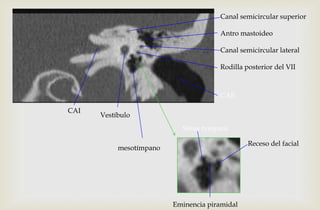

Canal semicircular superior

Antro mastoideo

Canal semicircular lateral

Rodilla posterior del VII

Vestíbulo

CAE

CAI

mesotímpano

Receso del facial

Eminencia piramidal

Sinus tympani